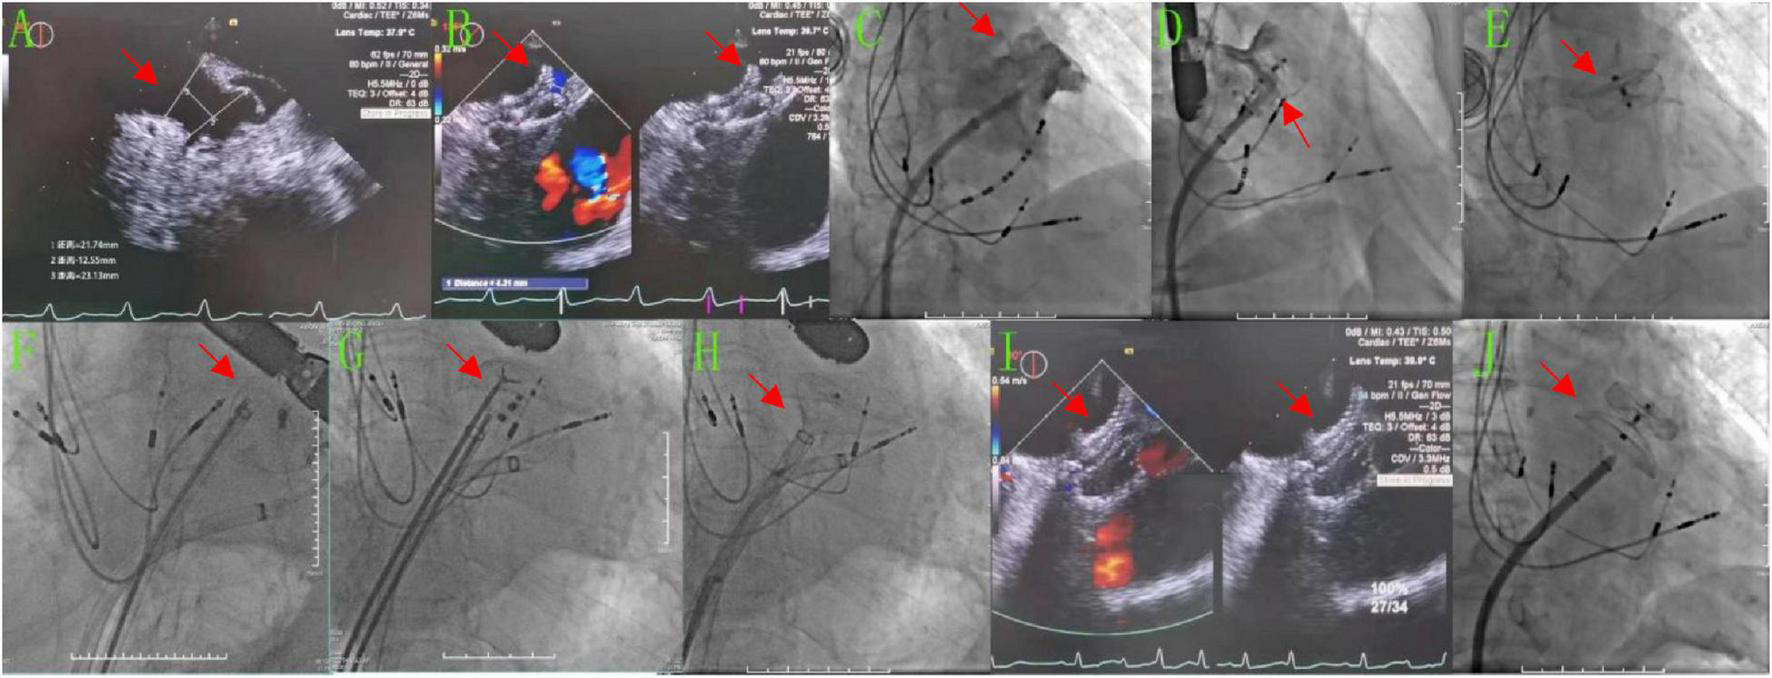

Case 2 involved an 86-year-old male patient with a history of persistent AF for 3 years and an implanted pacemaker because of bradyarrhythmia for 6 years. His CHA2DS2-VASc score was 5 points, and his HAS-BLED score was 2 points. After cryoablation, LAAC was performed, in which the diameter of the LAA opening as measured by TEE was 18.3–22 mm and the anchoring zone was 16.5–24.4 mm (Figure 2A). The LAA showed a chicken wing shape. The diameter of the opening of the LAA as measured by DSA was 28.6 mm, and the anchoring area was 31.5 mm (Figure 2C). A Lacbes 2834 device was delivered (Figure 2D). TEE showed that the shoulder of the fixed column was mildly exposed, and the residual shunt at the upper edge was 4.3 mm, which was within the allowable range. The occluder was slowly released after pulling it steadily (Figure 2B). After returning to the ward, the patient had no chest tightness or shortness of breath, but he did complain of drowsiness, and his blood pressure dropped to 58/41 mmHg, with a heart rate of 60 beats/min. Subsequently, dopamine 20 mg was administered intravenously while increasing the rate of fluid replacement to maintain blood pressure. Bedside echocardiography showed that the occluder had drifted in the LA, and the possibility of the occluder detaching was considered. Emergency LAA occlusion umbrella capture was performed under general anesthesia with endotracheal intubation and ventilator-assisted breathing. Under DSA, the occluder was seen floating in the LA (Figure 2E). The atrial septal puncture was performed twice through the right femoral vein route. Two 14-Fr cryoablation steerable sheaths were sent to the LA. A pigtail catheter (Terumo) was delivered across the mitral valve to prevent the occluder from crossing the mitral valve and traveling into the LV. The Raptor grasping device and pigtail catheters were sent through another sheath, and the latter was used to attempt to fix the occluder in an appropriate position, i.e., coaxial alignment of the jaws of the Raptor grasping device to the center of the Lacbes disc. Once the disc was grasped, sustained traction initially dislodged the proximal disc from the LA, and the occluder was pulled back to the sheath (Figures 2F–H); then, the Lacbes 2636 device was placed in the LAA (Figures 2I,J). After discharge, warfarin was used to control the international normalized ratio (INR) to 2–3. Results of the 3-month postoperative follow-up re-examination of TEE were normal. Long-term oral administration of clopidogrel antiplatelet drugs was enacted. During the follow-up period, the patient’s quality of life was good, and persistent follow-up will be conducted.

FIGURE 2

After LAAC, the occluder detached into the LA and was retrieved, before the Lacbes 2834 device was occluded again. (A,B,I) TEE images. (A) Preoperatively, the diameter of the LAA opening was 18.3–22 mm and the diameter of the anchoring area was 16.5–24.4 mm. (B) The Lacbes 2834 was placed in LAA, the fixed column was exposed, and the residual shunt at the upper edge was 4.3 mm. (I) After the second LAAC procedure with Lacbes 2636, the covering disc adhered well and had no residual shunt. (C–H,J) DSA images. (C) Preoperatively, the diameter of the LAA change opening was 28.56 mm and the diameter of the anchoring area was approximately 31.47 mm. (D) After closure with the Lacbes 2834 device. (E) The Lacbes fell into the LA. (F–H) Endoscopic Raptor forceps were used to clamp the umbrella trabeculae and drag them into the sheath. (J) After the second LAAC procedure with the Lacbes 2636 device.